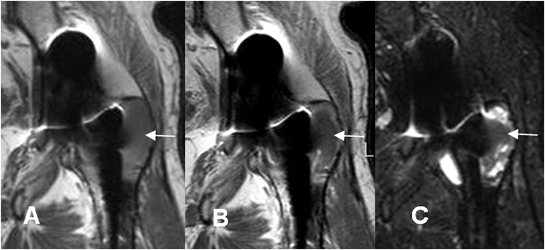

Fig 126 F. Granulomatosis agresiva.

A: RM coronal en T1, B: RM coronal en T2 , C: RM coronal en STIR y D: RM coronal en T1 con contraste. Igual paciente anterior. La imagen del ramo isquiopúbico muestra consistencia quística y realce periférico del contraste.